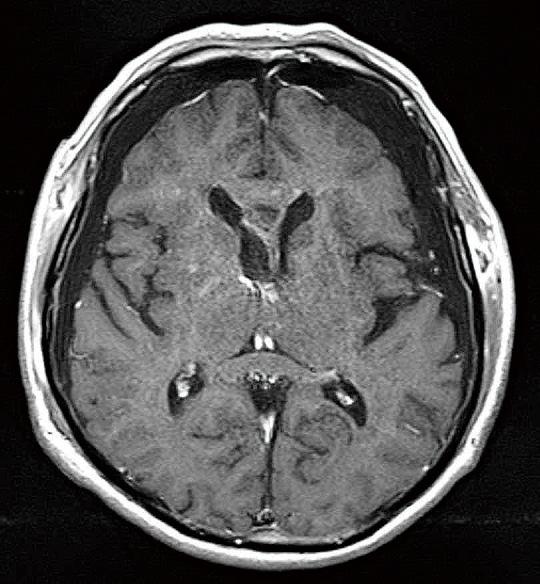

Subependymoma (SE) is a rare, usually asymptomatic, brain tumor predominantly affecting older adults and occurring in the fourth and lateral ventricles. We report a rare case of SE with intratumoral hemorrhage that could be removed by neuroendoscopy. The 81-year-old patient had been followed as an outpatient for 10 years due to an intraventricular tumor. It did not grow over the patient's lengthy follow-up. The patient was transferred to our hospital after he fainted near his home; at the time of admission, he had mild consciousness disturbance, and his Glasgow Coma Scale score was 10 points (E3V3M4). Computed tomography showed intratumoral hemorrhage and slight ventricular enlargement. Magnetic resonance (MR) imaging showed a 4 cm-sized tumor in the anterior horn of the right lateral ventricle. The lesion appeared as a mixed-intensity solid tumor and showed irregular enhancement with gadolinium. The patient underwent neuroendoscopic tumor resection on the 30 day of the patient's hospital stay. A histopathological examination revealed small tumor cells with round nuclei scattered in the glial fibrillary background. Immunostaining was positive for glial fibrillary acidic protein; these findings are consistent with an SE diagnosis. The patient in this study had hypertension and used anticoagulants, risk factors for intratumoral hemorrhage. For intraventricular tumors with bleeding-particularly in older or more physically frail patients-minimally invasive neuroendoscopic surgery should be considered an option for tumor resection.

室管膜下瘤(SE)是一种罕见的、通常无症状的脑肿瘤,主要影响老年人,多发生于第四脑室和侧脑室。我们报告一例罕见的伴有瘤内出血的室管膜下瘤,该肿瘤可通过神经内镜切除。这位81岁的患者因脑室内肿瘤已作为门诊患者随访了10年。在患者漫长的随访期间肿瘤未生长。患者在家附近晕倒后被转至我院;入院时,他有轻度意识障碍,格拉斯哥昏迷量表评分为10分(E3V3M4)。计算机断层扫描显示瘤内出血和轻度脑室扩大。磁共振成像显示右侧脑室前角有一个4厘米大小的肿瘤。该病变表现为混合密度实性肿瘤,钆增强扫描显示不规则强化。患者在住院第30天行神经内镜肿瘤切除术。组织病理学检查显示圆形核的小肿瘤细胞散在于胶质纤维背景中。免疫染色胶质纤维酸性蛋白呈阳性;这些发现符合室管膜下瘤的诊断。本研究中的患者患有高血压并使用抗凝剂,这些都是瘤内出血的危险因素。对于伴有出血的脑室内肿瘤,尤其是老年或身体较为虚弱的患者,微创神经内镜手术应被视为肿瘤切除的一种选择。